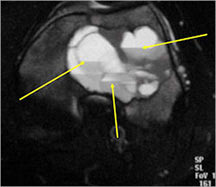

MRI/CT:

- Fluid-fluid levels secondary to cystic cavities filled with blood products. The sediment from blood products settle to the gravity dependent area of the cavity and the fluid component floats to top thus forming a fluid-fluid level.

- MRI and CT are also useful for demonstrating the local extent of the tumor and any soft tissue mass